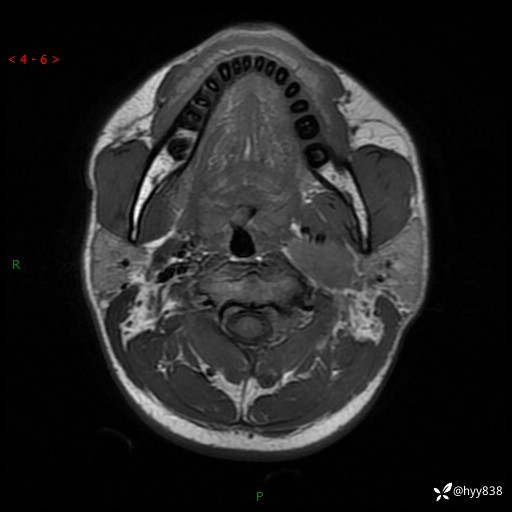

年轻小伙,发现左侧颈部肿物3年余,逐渐增大---结果公布~

现病史:患者约3年前因感冒发现左侧颈部长一肿物,约半个鸡蛋大小,无明显疼痛及其他不适,一直未行特殊处理。3个月前发现左侧颈部肿物变大,随后至当地市第二人民医院耳鼻喉科行左侧颈部彩超示:左侧颈部囊实混合性包块;喉部MPR示:左侧胸锁乳突肌内前方占位,累及左侧喉旁间隙,建议增强扫描。建议手术治疗。患者考虑。随后至我院肿瘤科就诊,行细胞学穿刺示:考虑血管源性肿瘤可能,建议进一步检查。建议至我院口腔科就诊,行颌面部MRI示:左侧颌下腺后方团状异常信号灶,建议增强。建议手术治疗。为求进一步治疗,门诊以“左侧颈部肿物”收入院。 起病以来,患者神志清、精神良好,饮食睡眠良好,大小便正常,体重未见明显变化。

颈部MRI平扫+增强